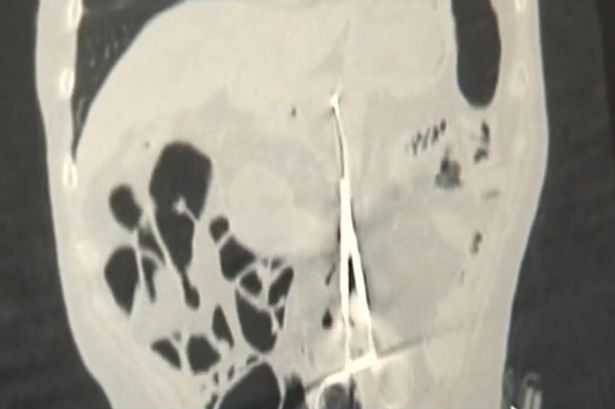

Dopo essersi rassegnato a provare dolore perennemente, Karp da un mese aveva cominciato a dimagrire perdendo anche l’appetito. Ha così pensato di recarsi all’ospedale per una visita e lì, grazie ai raggi x, hanno scoperto l’arcano.

Le forbici che aveva nello stomaco era quelle utilizzato da chirurghi e lunghe quasi 20 centimetri. I medici hanno raccontato di non aver mai visto niente del genere.